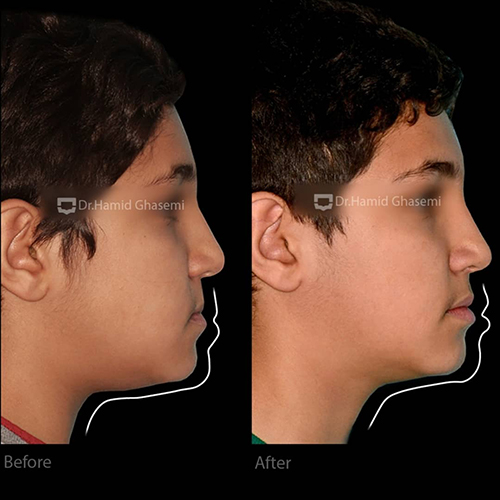

- عقب بدن لب بالا

- تأثیرات نامطلوب عقب بودن فک بالا بر روی حالت لب بالا و گونهها

در مرحله اول، با استفاده از اکسپاندر و پیچهای داخل کامی جهت شل شدن درز بین فکی در فک بالا و سپس اعمال نیروی خارج دهانی فیس ماسک جهت جابهجایی فک بالا به سمت جلو انجام شد.

- جابهجایی فک بالا به سمت جلو

- حرکت به سمت جلو و بهبود حالت بافت نرم لبهای بالا و گونهها به سبب حرکت رو به جلو فک بالا